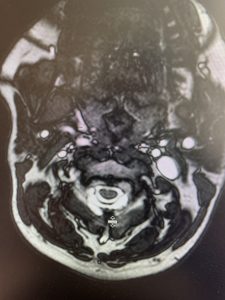

This 57 year-old male presents with severe neck, left shoulder and arm pain and weakness in his hand since being involved in a motor vehicle accident nine months prior. The patient had subsequent left shoulder surgery although he still complained of pain postoperatively and his weakness persisted. He was on no blood thinners. He underwent imaging. The cervical spine MRI revealed an extensive dorsal epidural collection from C1-2 through C5 with associated spinal cord compression. In addition there were multisegmental degenerative changes with foraminal stenosis worse at C4-5 (Fig. 1a and 1b).

(1a) Sagittal and axial T2-weighted cervical MRI demonstrating extensive dorsal epidural collection with hyperintense signal consistent with fluid causing spinal cord compression.

(1b) Hyperintense signal (arrow) at the C3-4 interspinous space consistent with ruptured interspinous ligament,C4-5 (Fig. 1a and 1b).